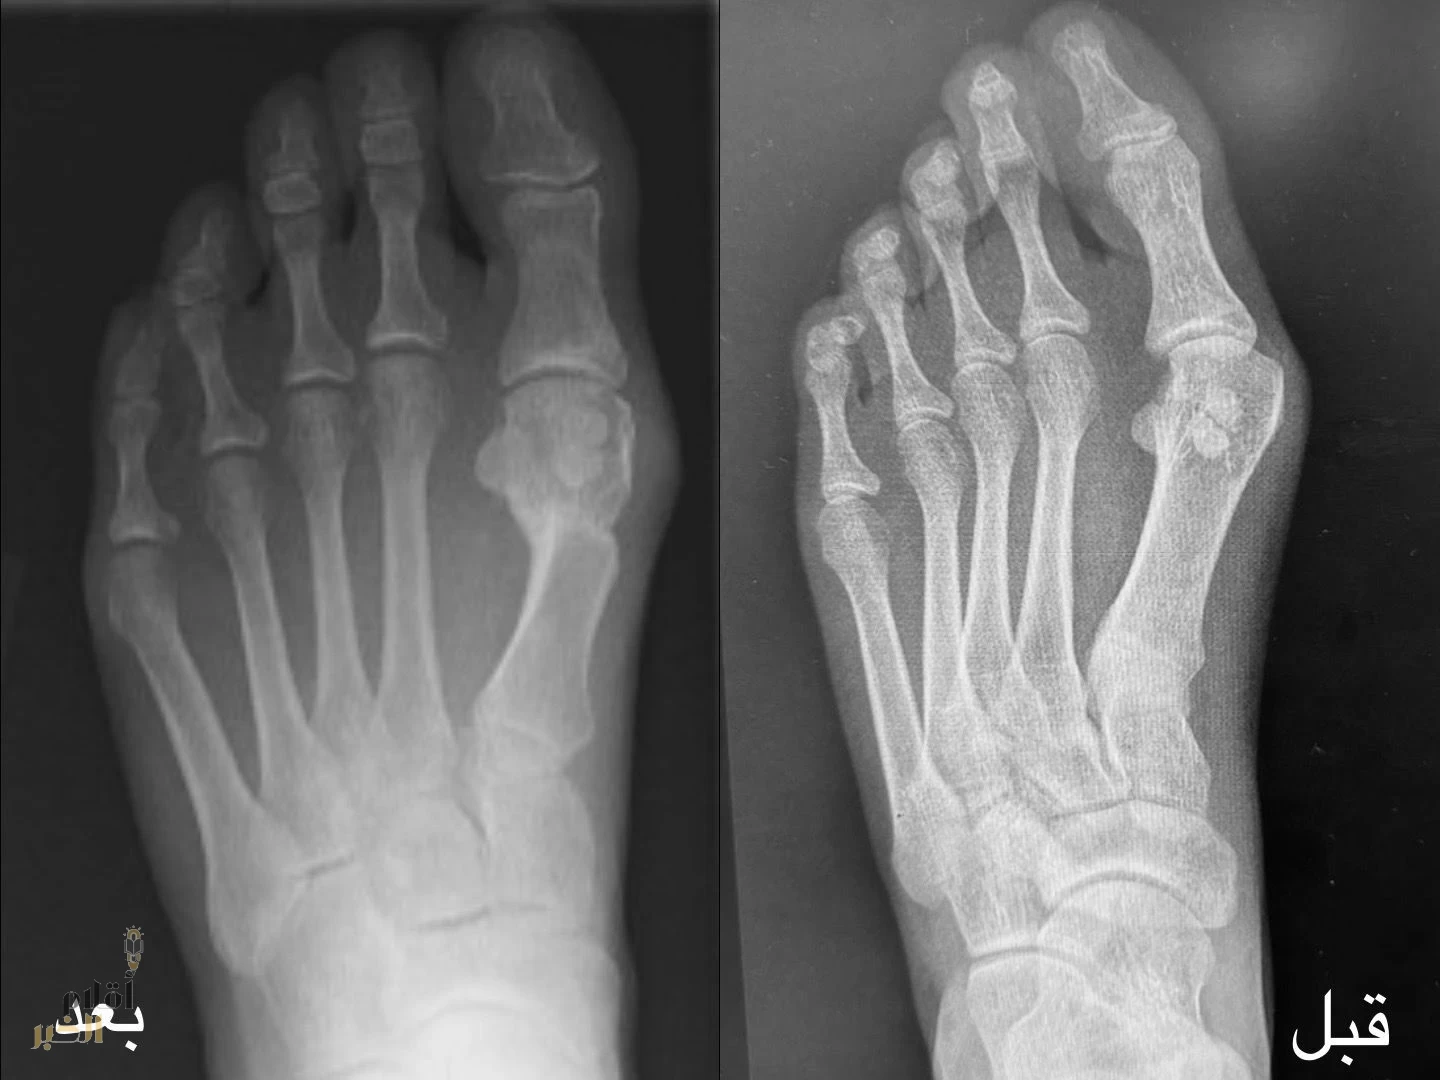

نجح فريق طبي في قسم جراحة العظام بمستشفى الإمام عبدالرحمن الفيصل، عضو تجمع الرياض الصحي الأول، في إجراء عملية نوعية باستخدام تقنية التدخل الجراحي المحدود (MIS)، لتصحيح تشوّه وانحراف إصبع القدم الكبير (Hallux Valgus)، لمريضة في العقد الثاني من عمرها كانت تعاني من تشوّه متقدم أثّر على حركتها ونشاطها اليومي.

وأوضح رئيس قسم جراحة العظام وقائد الفريق الطبي، الدكتور عقيل محمد المهدلي، أن المريضة خضعت لسلسلة من الفحوصات السريرية والأشعة التشخيصية قبل اتخاذ القرار الجراحي، حيث أُجريت العملية وفق أحدث المعايير الطبية المعتمدة، ولله الحمد تكللت بالنجاح التام.

وأشار إلى أن المتابعة بعد العملية أظهرت تحسنًا ملحوظًا في وظيفة القدم، حيث أصبحت المريضة قادرة على المشي بشكل طبيعي، وممارسة الرياضة، وارتداء مختلف أنواع الأحذية دون آلام، ما انعكس إيجابًا على جودة حياتها.